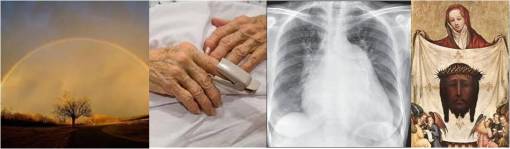

The official board that was established by the Vatican in the mid-1900s to analyze reported miracles consists of about 100 Italian, mostly Catholic physicians. For the initial review, a panel of five Consulta Medica doctors review the case including all CT scans, X-rays, and medical reports provided. Once this review is complete, at least three of the five must agree that ‘God has prevailed where science faltered’. Once these results are determined, a case is reviewed by the entire committee of physicians who then decide upon a formal decision. This is then sent to a panel of cardinals and priests who must determine whether of not the cure is the result of praying to a saintly candidate. If this panel decides the evidence of healing prayer does exists, then the miracle is approved as such, and the panel issues its final conclusion in the form of a declaration.

The completion of this change is not at all proven. This is the most common error in proving that a change and cure has taken place. The possibility of simple remission has not been excluded. To demonstrate cure versus remission, a longer period of time would have to elapse after the change in order to demonstrate that an actual cure has happened. In some cases, only a few tests and days of evaluation may be all that is needed to decide whether or not a true change occurred. This is seen with cancer cases, and especially with all the tuberculosis cases cured through miracles. In the case of cancer, a series of x-rays and MRIs proves or disproves the change needed to demonstrate a cure. In cases of chronic disease like diabetes, multiple sclerosis, epilepsy, etc., to demonstrate a cure has happened and not a simple remission, the case may have to be followed up for a year or two.

The purpose of lab tests and an x-ray is to show that the rheumatism has stopped, such as through a reduction in Rheumatoid Factor, accompanied by a decrease in symptomatology (pain and swelling), without a history of prescription drug use.